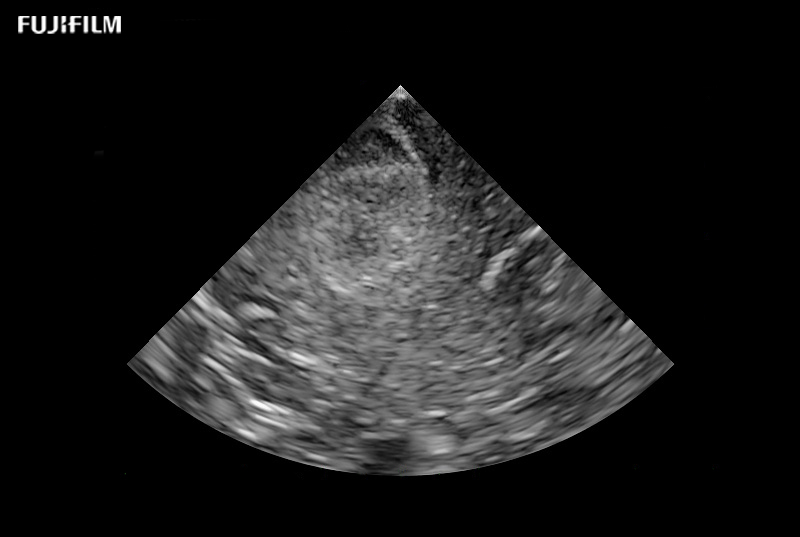

Liver Spectral Doppler using C22I

Curved array deep penetration “I” style finger-grip transducer for open kidney surgical procedures. Allows for palpating organs and scanning at the same time.